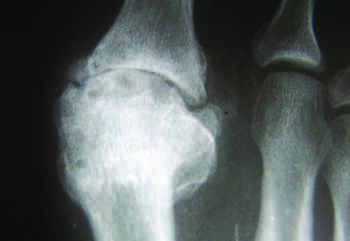

Stage 3. In stage 3, the patient has lost nearly all motion in the first MPJ, now with less than 10 degrees of dorsiflexion remaining, and movement of the joint to the end range of motion causes the patient significant pain.17 Radiographically, there will be significant joint space narrowing, joint destruction, and with possible sesamoid change. This stage by definition constitutes a hallux rigidus.

Stage 4. This stage is similar to stage 3, except any motion at the first MPJ causes the patient pain.17 Radiographs will demonstrate arthrosis of the joint, with osteophytic changes of both the metatarsal head, and base of the proximal phalanx.

Radiographic findings may be subtle or negative in the early phases of the condition.18 As the condition progresses, radiographic findings may reveal joint narrowing, thinning of articular surfaces, osteophytic changes of the base of the proximal phalanx, spurring of the metatarsal head, and possible fracture fragments/loose bodies. If previous injury to the sesamoids occurred, there may be degenerative changes there as well.18